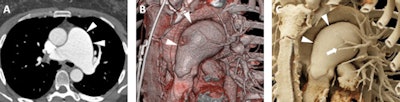

Specifically, a cinemetic rendering of the aorta ahead of such endovascular repair is likely to prove useful. In the figure below, a very narrow coarctation is depicted in high detail by cinematic-rendered images. The quality is sufficient to demonstrate this aortic pathology to patients, clearly showing them how the blood flow is compromised by the aortic constriction, as well as the mechanism of repair, the authors noted.

A 59-year-old man who was experiencing exercise intolerance and was found to have widely disparate upper and lower extremity blood pressures. A: Axial postcontrast 2D CT image demonstrates marked narrowing/coarctation of the aorta (white arrowhead) just distal to the takeoff of the left subclavian artery. B: Cinematic rendering image displays the coarctation in 3D (white arrowhead) with realistic shadowing effects and a detailed depiction of the relative positions of other vascular structures such as the immediately inferior left main pulmonary artery. C: Another cinematic-rendered visualization demonstrates representative collateral vessels (bilateral internal mammary arteries, white arrows).Furthermore, although the data are not yet available to compare cinematic-rendered prosthetic valve evaluation with traditional evaluation with volume-rendered images, the new methodology may improve diagnosis of subtle complications, such as early bioprosthetic valve degeneration or the formation of small thrombi.